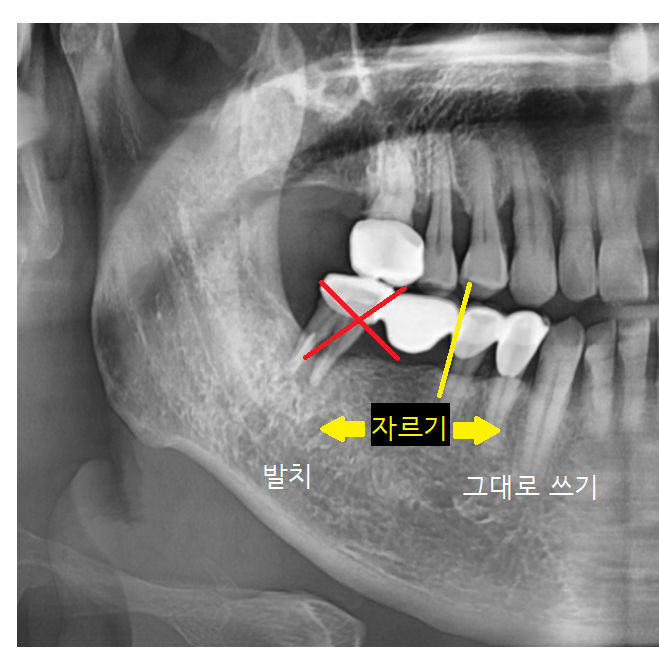

사진 속 화살표 치아를 주목해 주세요.

브릿지 치료가 되어있네요.

4개가 연결되어 있지만

검사 후 잇몸뼈가 남아있는 부분은

그대로 쓰시기로 했습니다.

연결된 오래된 브릿지 보철을 잘라서

뽑을 건 뽑고

살릴 수 있는 것은 살려서 진행